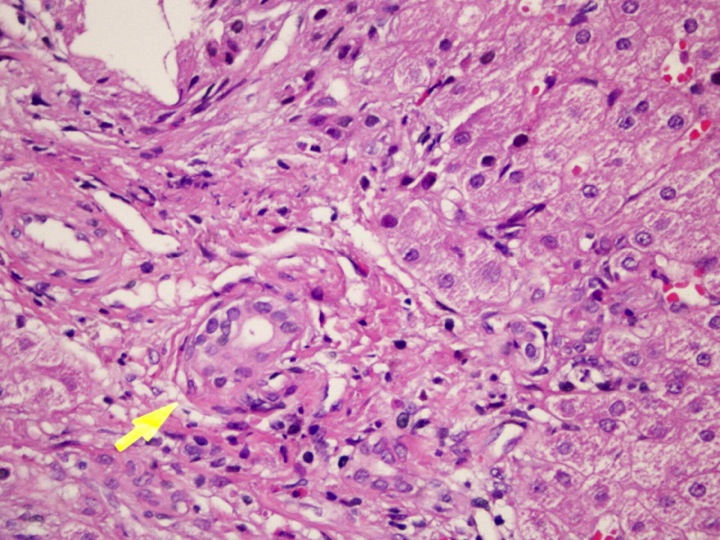

En la biopsia realizada a la paciente, se observa una arquitectura hepática alterada por la presencia de proliferación de tejido conjuntivo e infiltrado inflamatorio que rompe la lámina limitante. Proliferación de conductillos que en ocasiones están dañados. Focos inflamatorios en el parénquima y hepatocitos balonizados. En conclusión, hepatitis crónica activa, grado 3/6 de fibrosis y 9/18 de actividad, compatible con etiología autoinmune.